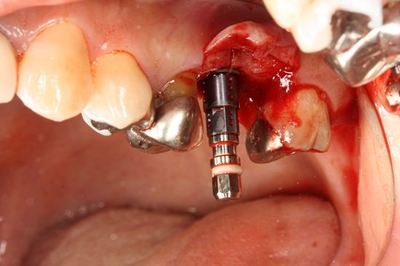

いよいよ本日のオペを行います。

ミラー像

前後の金属も今後除去していきます。

![]()

ドリルガイドの適合を確認します。